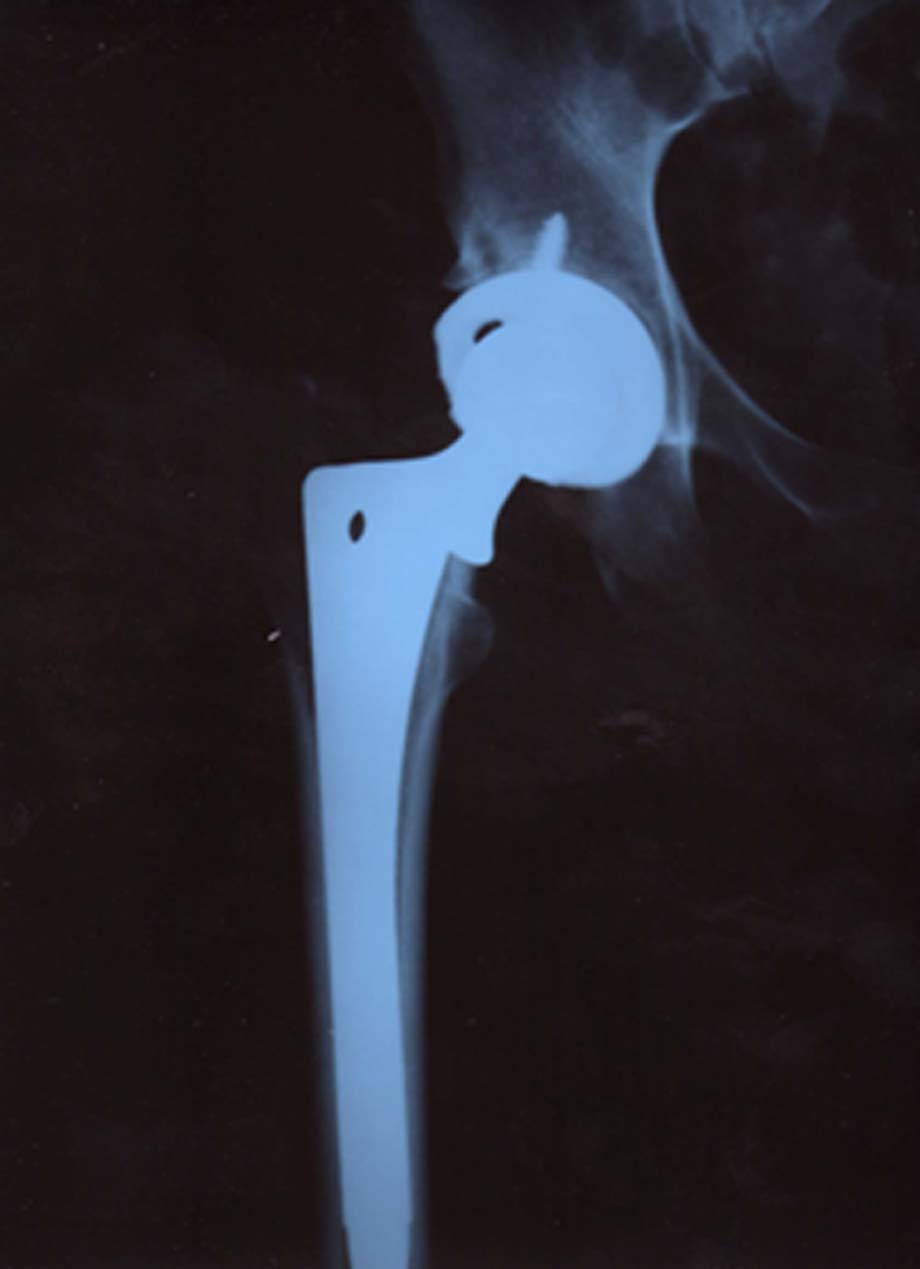

Both Posterior and Anterior Procedures by Robert Klapper, MD and Robert Klenck, MD

Post Op for the Anterior Approach (with Matta’s procedure – what a Genius method) is at SIX WEEKS.  Different than post op for Posterior – which is at two weeks.  At six weeks, they can see, by Xray, how the stem has fused into the bone.  It is then that you can resume swimming and even BEFORE then that you can drive and go back to work.